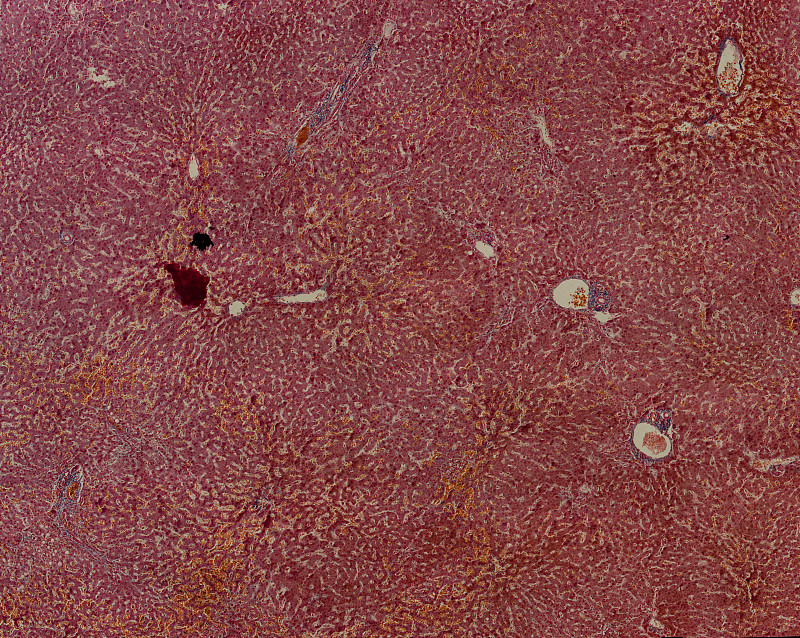

显微镜下的人肝细胞详情

JPG